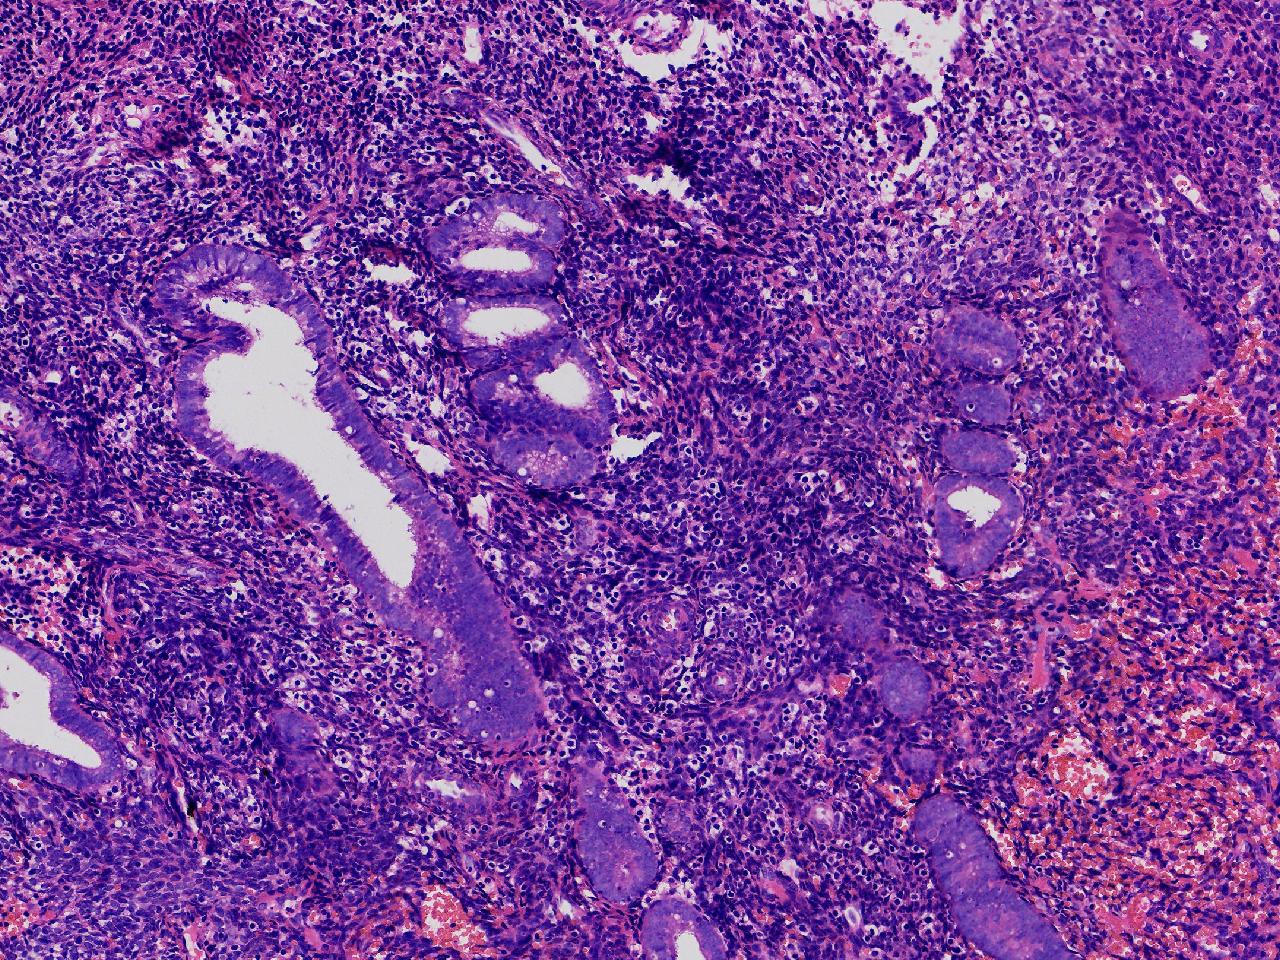

请教诊断。局灶够不够非典?

性别

女

年龄

44岁

阴道不规则出血20余日,彩超示:内膜线居中,厚15毫米。

子宫内膜

灰粉色不整形软组织多块,3X2X1厘米。

不够非典

有输卵管上皮化生,感觉不够非典。